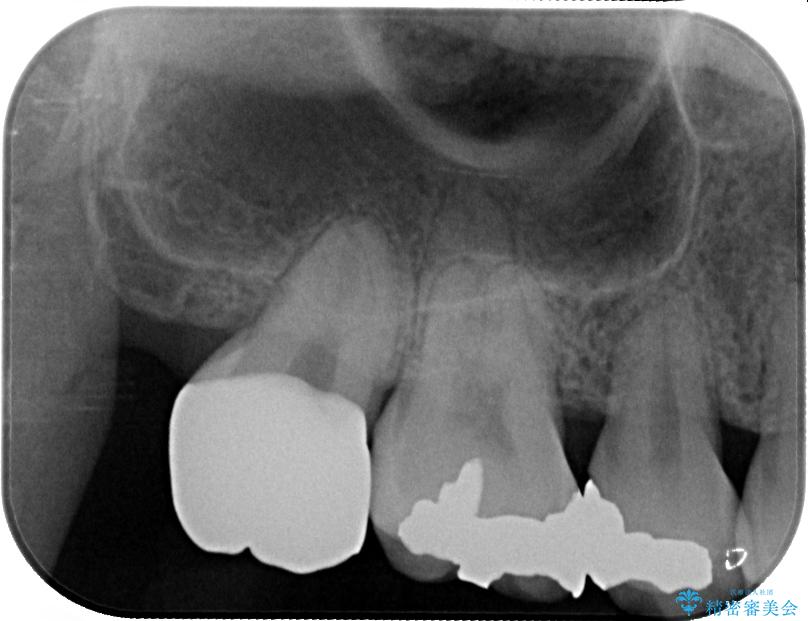

セラミッククラウンの適合はレントゲン写真からも分かる通り、境界がぴったりと合った、高適合のものとなりました。